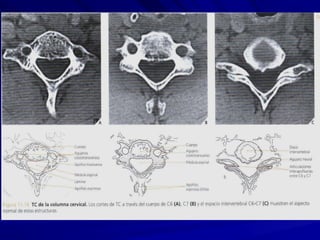

VERTEBRAS CERVICALESVERTEBRAS CERVICALES

1.- CUERPO: rectangular1.- CUERPO: rectangular

2. AG.VERTEBRAL: triangular.2. AG.VERTEBRAL: triangular.

3. AP.TRANSVERSA:3. AP.TRANSVERSA:

bifurcada/agujero transverso.bifurcada/agujero transverso.

arteria y vena vertebral 1-6arteria y vena vertebral 1-6

vena vertebral … 7.vena vertebral … 7.

4. AP. ESPINOSA: bifurcada.4. AP. ESPINOSA: bifurcada.

5. AP.ARTICULARES:5. AP.ARTICULARES:

superiores arribasuperiores arriba

inferiores abajoinferiores abajo

CARACTERISTICA PRINCIPALCARACTERISTICA PRINCIPAL::

AGUJERO TRANSVERSOAGUJERO TRANSVERSO

VERTEBRAS CERVICALESVERTEBRAS CERVICALES 1.-CUERPO: rectangular1.- CUERPO: rectangular 2. AG.VERTEBRAL: triangular.2. AG.VERTEBRAL: triangular. 3. AP.TRANSVERSA:3. AP.TRANSVERSA: bifurcada/agujero transverso.bifurcada/agujero transverso. arteria y vena vertebral 1-6arteria y vena vertebral 1-6 vena vertebral … 7.vena vertebral … 7. 4. AP. ESPINOSA: bifurcada.4. AP. ESPINOSA: bifurcada. 5. AP.ARTICULARES:5. AP.ARTICULARES: superiores arribasuperiores arriba inferiores abajoinferiores abajo CARACTERISTICA PRINCIPALCARACTERISTICA PRINCIPAL:: AGUJERO TRANSVERSOAGUJERO TRANSVERSO